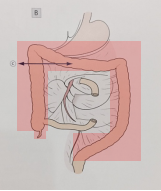

手术切除的范围

末端回肠折叠制作储袋、进行肛管储袋吻合